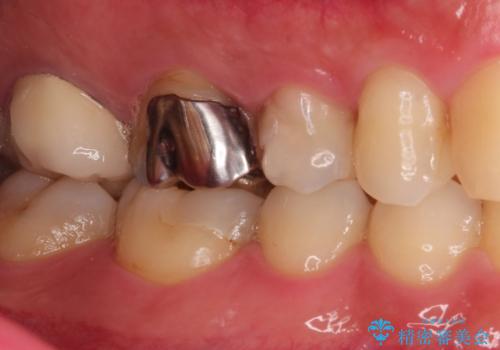

- 定期検診にて不良補綴物、及び虫歯を認めオールセラミッククラウンにて治療を行いました。

右上第二小臼歯はカリエス除去中に露髄を認め、部分的断髄法にて歯髄を保存しております。